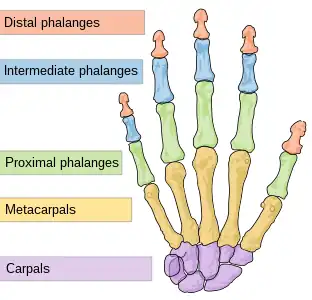

The DIP, PIP and MCP joints of the hand:

The interphalangeal joints of the hand are the hinge joints between the phalanges of the fingers that provide flexion towards the palm of the hand.

There are two sets in each finger (except in the thumb, which has only one joint):

- "proximal interphalangeal joints" (PIJ or PIP), those between the first (also called proximal) and second (intermediate) phalanges

- "distal interphalangeal joints" (DIJ or DIP), those between the second (intermediate) and third (distal) phalanges